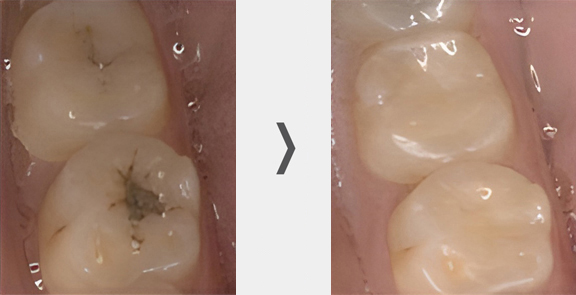

Before

After

When a tooth decays and becomes damaged, several treatment options are available depending on the size and severity of the cavity. The most common cavity treatments are as follows:

For relatively small to mid-sized cavities, a composite resin filling is recommended. It is made of a plastic resin reinforced with powered glass, allowing for a color match to the surrounding teeth.

Only one visit is required for this treatment.